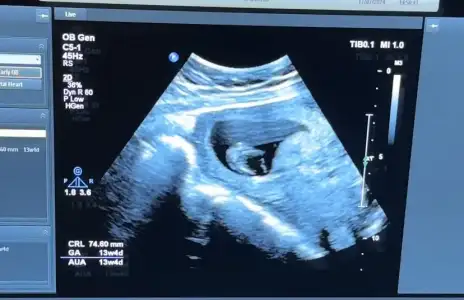

Kızlar öncelikle sağlıkla gelsin bebişlerimiz. Ben cinsiyetle alakalı bir şey sormak istiyorum. Baştan beri kız hissediyorum ilk bebegim ve 3 kez rüyamda kız gördüm. Hatta üçüncüsü çok netti suratını bile çizebilirim. Ama iki doktora gittim ikisi de erkek dedi 13-14. Haftada falandık sanırım. Şuan 16 olmak üzere. Acaba yanılma ihtimalleri var mı ben hala kız oldugunu hissediyorum rüyalardan dolayı kafam çok karışık.

Yanılma olabilir canım ben 12 haftada Medical park Keçiören hastanesinde çok iyi bi doktora gittim ve kesin erkek dediler ama ben hep kız hissediyorum hiç inanmadım 15.ve 17 haftada devlet hastanesine gittim ve bu bebek kız dediler kesinleşti kız olduğu Allah gönlüne göre versin inşallah